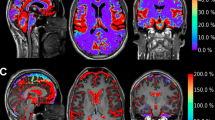

To determine if CSF from patients with communicating hydrocephalus, obstructive hydrocephalus and control subjects showed a distinct proteomic profile; data were plotted as a volcano plot to visualize the profiles of the groups (Fig. 1). When CSF from communicating hydrocephalus patients was compared to CSF from control subjects, four proteins, vimentin (VIM), protocadherin alpha subfamily C2 (PCDHAC2), glutathione synthetase (GSS), and prolyl 4-hydroxylase subunit beta (P4HB), were found in significantly higher abundance in control subjects (Fig. 1a and Table 2). When comparing obstructive hydrocephalus to controls, only vimentin (VIM) was found to show a higher abundance in controls (Fig. 1b and Table 3). When the obstructive hydrocephalus group was compared to the communicating hydrocephalus group, we found one protein, syndecan binding protein (SDCBP), to differ significantly, with higher abundance in obstructive hydrocephalus (Fig. 1c and Table 4). In accordance with these few differences in the proteomic group profiles, the PCA plot did not reveal distinct proteomic distributions of either obstructive hydrocephalus, communicating hydrocephalus, or control samples (Fig. 2). All proteins detected by the MS-based analysis, which were included in the three comparisons in Fig. 1, are listed in Supplementary information 2, 3, and 4.

A PCA plot of CSF samples from control subjects and patients with communicating or obstructive hydrocephalus. The plot shows no clear clustering of proteomic profiles of different types of hydrocephalus and controls. Patients with communicating hydrocephalus: n = 62; patients with obstructive hydrocephalus: n = 28; control subjects: n = 10; ctrl: controls; PCA: principal component analysis; HC: hydrocephalus